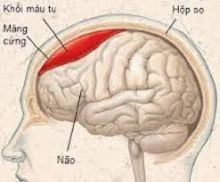

Dị dạng động tĩnh mạch (AVMs) là các đám rối mạch máu bị giãn, trong đó các động mạch dẫn máu trực tiếp vào tĩnh mạch. AVM thường gặp nhất ở chỗ nối của các động mạch não, thường là trong nhu mô não vùng trán - đỉnh, thùy trán, tiểu não bên, hoặc thùy chẩm. AVM cũng có thể gặp ở màng cứng.

Xuất huyết do AVM não thường là trong nhu mô nhưng có thể dưới nhện hoặc trong não thất.